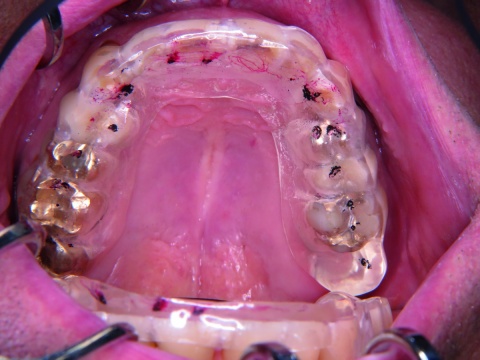

Die Herstellung der Schiene erfolgte aus einem transparenten Kunststoff. Bei Eingliederung waren Schienensitz (kein Wackeln) und Schienenhalt gut. Der Patient war in der Lage, die Schiene selbst herauszunehmen und wieder richtig auf den Zähnen zu platzieren.

Anschließend wurden die Kontaktpunkte in statischer und dynamischer Okklusion überprüft. Ziel war es, eine „Front-/Eckzahn-geschützte Okklusion“ zu erreichen. Dazu wurde zuerst überprüft, ob stärkere Vorkontakte auf der Schiene vorhanden waren, was nicht der Fall war. Danach wurden die dynamischen Kontaktbahnen bei Protrusions- und Laterotrusionsbewegungen mit roter Okklusionsfolie und die statischen Kontaktpunkte mit schwarzer Okklusionsfolie markiert. Die Schiene wurde danach so eingeschliffen, dass eine gleichmäßige Abstützung der Seitenzähne in der Statik und eine Front-Eckzahnführung bei dynamischen Unterkieferbewegungen nach anterior oder nach lateral vorlag (Abbildung 3).

Abschließend wurden die durch die erfolgten Korrekturen an der Schiene aufgerauten Stellen wieder poliert. Der Patient erhielt den Hinweis, die Schiene konsequent nachts während des Schlafens zu tragen. Dadurch sollten die Zähne auch vor Abnutzungen durch nächtlichen Bruxismus geschützt und der Patient bei der Berufsausübung durch das Tragen einer Schiene nicht beeinträchtigt werden.